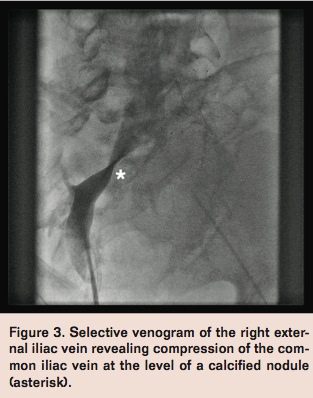

Access was then obtained in the right femoral vein to position a catheter at the inferior vena cava-common iliac vein bifurcation to accurately position the left common iliac vein stent. However, selective venography of the right femoral vein revealed compression of the right common iliac vein (Figure 3) at the level of a calcified nodule adjacent to the vein that was suspicious of arterial calcification. Access was then obtained in the right common femoral artery to further evaluate this finding.